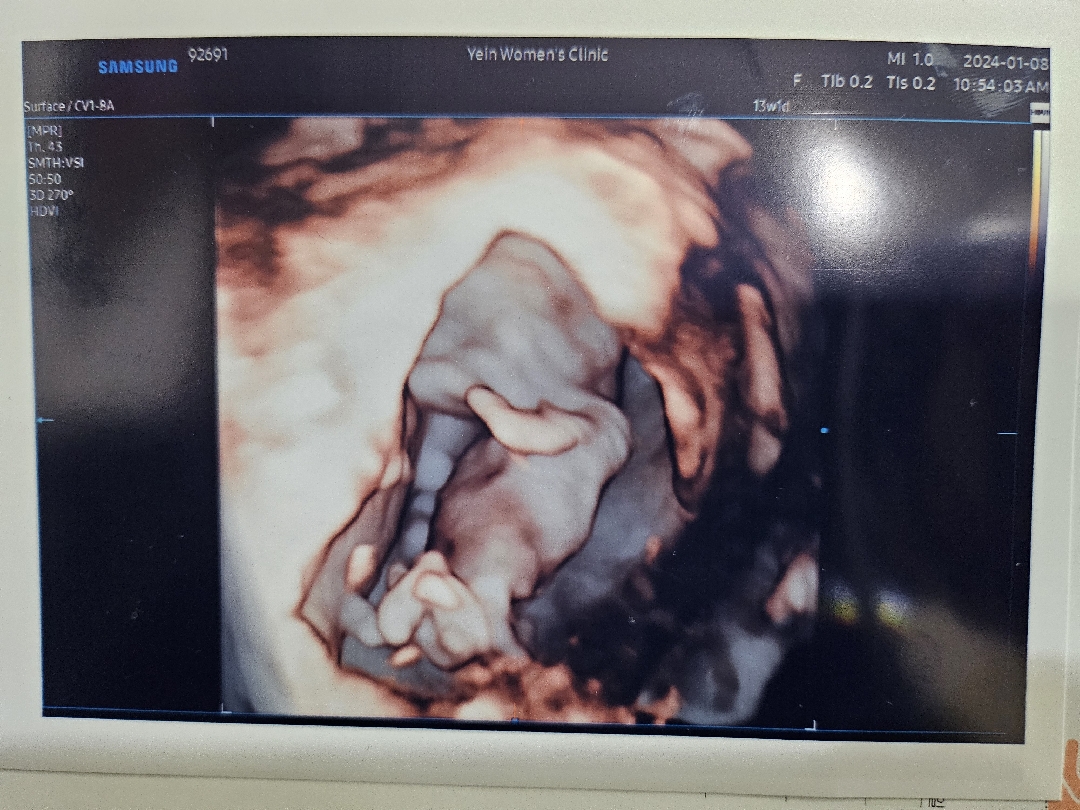

13주 되었는데 확실하진 않지만 딸일것 같다고 하는데 정말 딸일까요 ??!???

이사진으론 알 수 없어요 ㅠㅠㅋ옆으로 누운 초음파사진으로 각도를 봐야죵

딸이라고 하는것 같던데,,